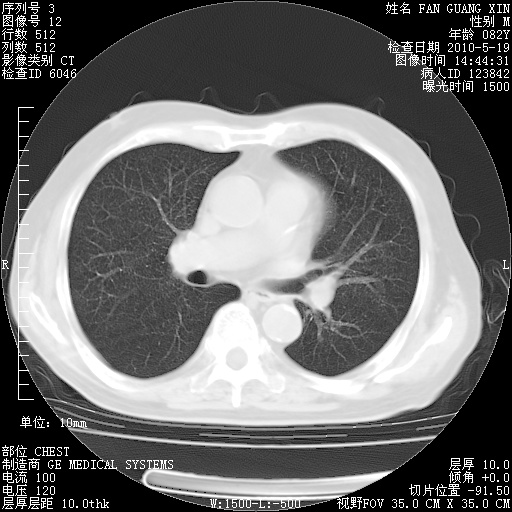

复查肺部CT,明显好转。为什么发热呢?

治疗3周后的肺部CT